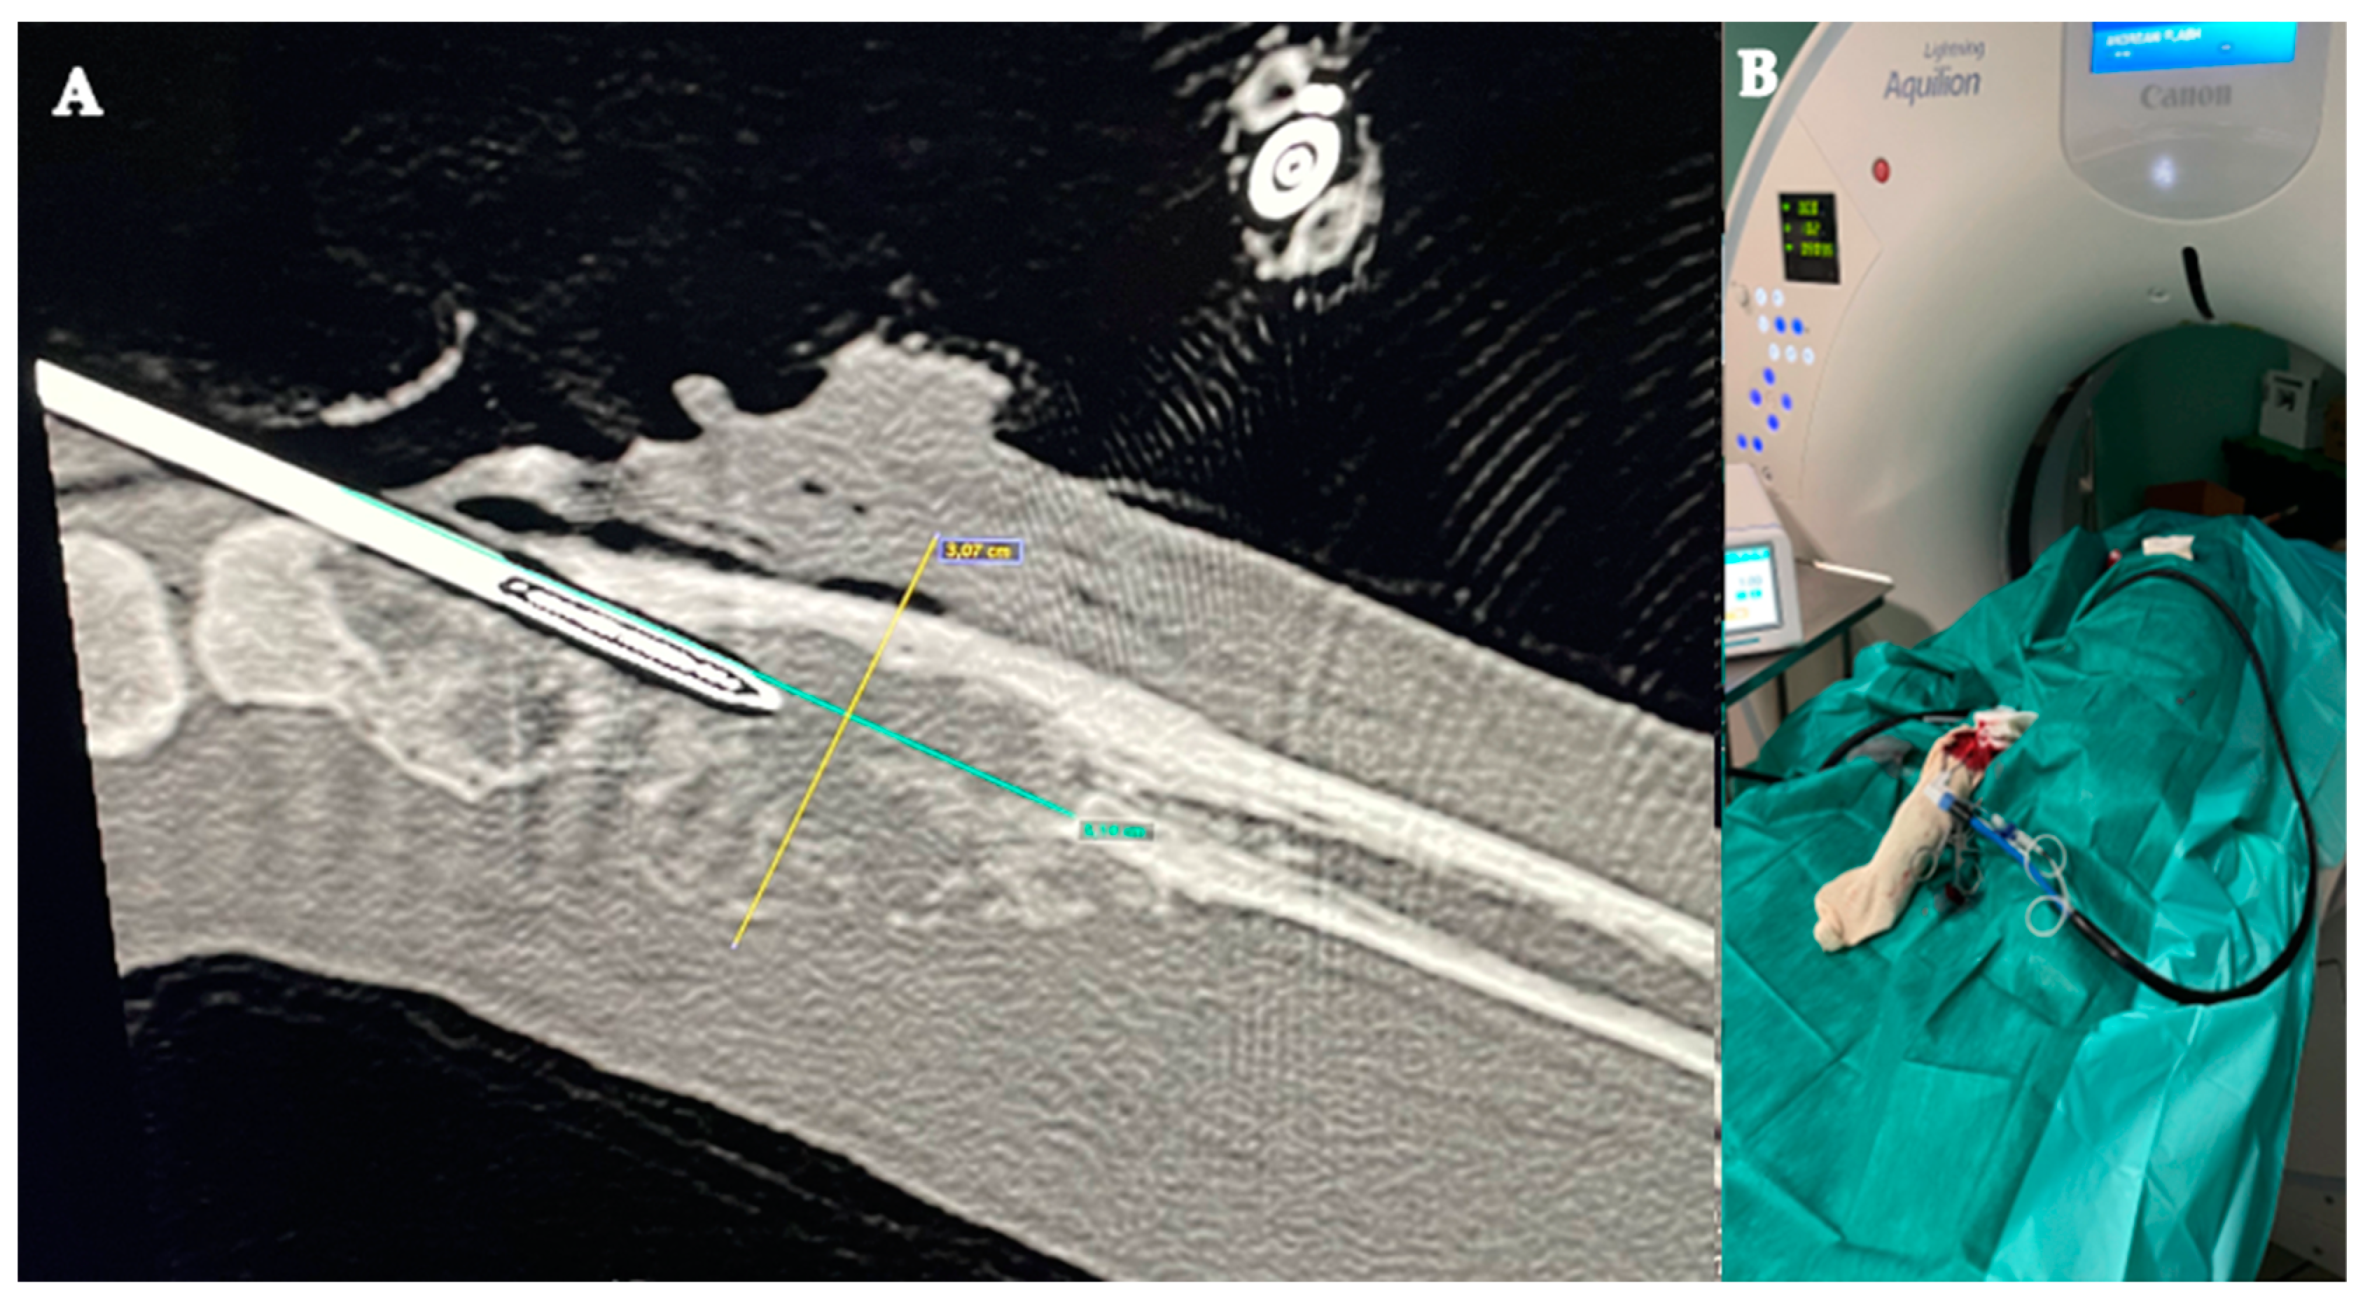

2.3. Microwave Ablation

2.4. Cementoplasty